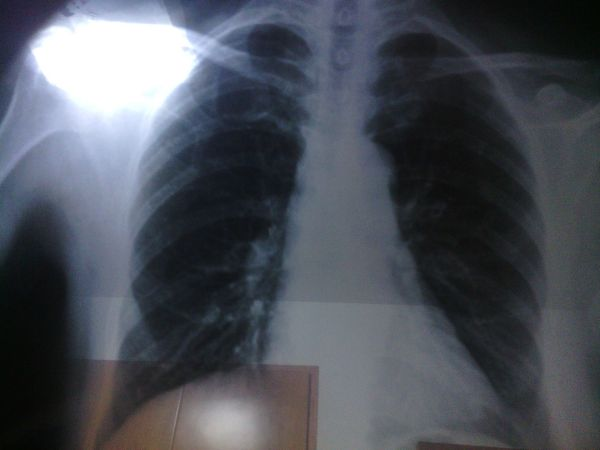

肺磨玻璃结节是胸部CT图像的学术语言。如果CT图像中的肺组织密度稍有增加,就会出现云雾状淡薄影。它的质地类似于磨砂玻璃,所以被称为磨玻璃结节。如果磨玻璃结节弥漫性存在于肺部,这通常是炎症的结果。如果是磨玻璃结节,则可能是恶性肿瘤。如果磨玻璃结节的直径小于8mm,建议定期检查并做出明确诊断。